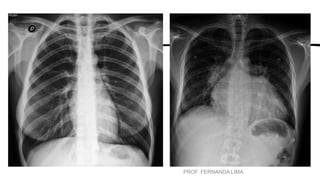

POSICIONAMENTOS DE ROTINA - TÓRAX

• INDICAÇÕES CLÍNICAS (P/ Posição Ortostática)

• •Derrames pleurais

• •Pneumotórax

• •Atelectasia e sinais de infecção.

• ROTINA BÁSICA TÓRAX

• •PA (Posteroanterior)

• •Perfil Esquerdo